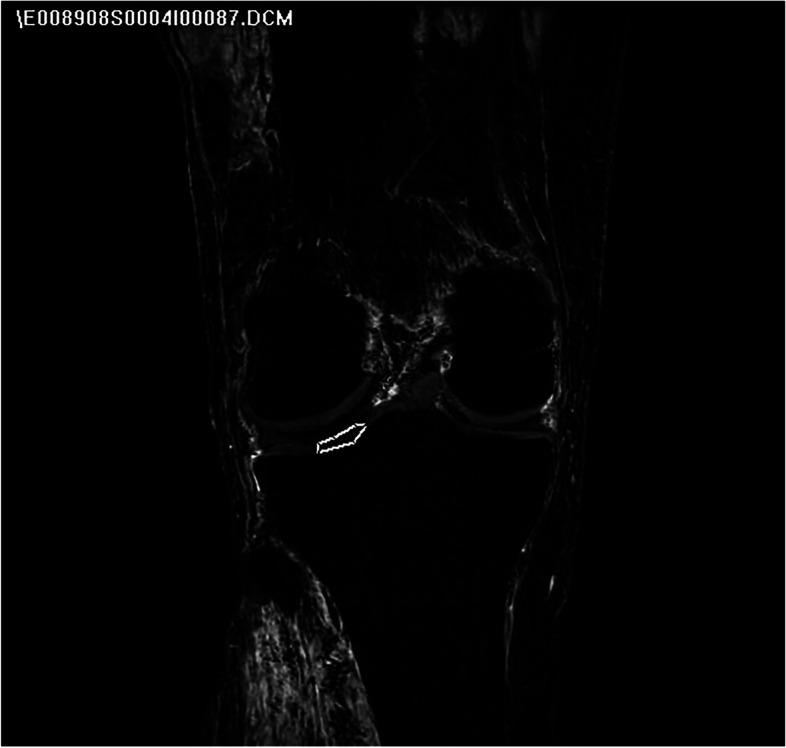

Fourteen cadaveric knees were studied (8 females, 6 males), age 25-61 years. Superficial femoral, anterior tibial, and posterior tibial arteries were cannulated; without intraarticular dissection. Contrast-enhanced quantitative-MRI was performed using a previously established protocol. ACL regions corresponding to proximal, middle, and distal thirds were identified on sagittal-oblique pre-contrast images. Signal enhancement (normalized to tibial plateau cartilage) was quantified to represent regional perfusion as a percentage of total ACL perfusion. Comparative statistics were computed using repeated measures ANOVA, and pairwise comparisons performed using the Bonferroni method.

Relative perfusion to proximal, middle, and distal ACL zones were 56.0% ±17.4%, 28.2% ±14.6%, and 15.8% ±16.3%, respectively (p = 0.002). Relative perfusion to the proximal third was significantly greater than middle (p = 0.007) and distal (p = 0.001). No statistically relevant difference in relative perfusion was found to middle and distal thirds (p = 0.281). Post-hoc subgroup analysis demonstrated greater proximal perfusion in males (66.9% ± 17.3%) than females (47.8% ± 13.0%), p = 0.036.

Using quantitative-MRI, in situ adult ACL demonstrated greatest relative perfusion to the proximal third, nearly 2 times greater than the middle third and 3 times greater than the distal third. Knowledge of differential ACL vascular supply is important for understanding pathogenesis of ACL injury and the process of biological healing following various forms of surgical treatment.